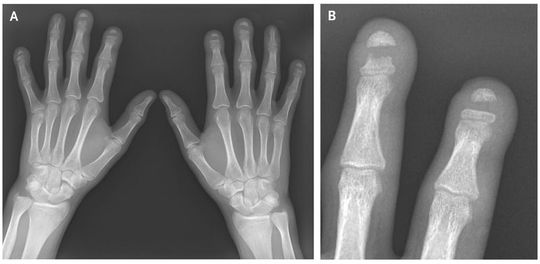

A 23-year-old male construction worker with a history of autoimmune sclerosing cholangitis presented with a 3-year history of coldness affecting both hands, triphasic Raynaud’s phenomenon, and tightening of the skin. Physical examination revealed mild clubbing of the fingers; patchy, nodular thickening of the skin on the hands and forearms; and linear plaques of fibrosis extending proximally past the elbows. His serum was positive for antinuclear antibody (titer, 1:1280) in a homogeneous pattern. Tests for anti–double-stranded DNA, anti-ribonucleoprotein, and anti-Scl-70 antibodies were negative. Plain radiographs of the hands showed sharply demarcated osteolysis of the midshaft of the distal phalanges of the index, middle, and little fingers on both hands and of the left ring finger (Panel A, with Panel B showing an enlarged image of the middle and index fingers of the left hand). This rare finding, known as band acro-osteolysis, has been associated with exposure to polyvinyl chloride (PVC) and with the Hadju–Cheney syndrome. The patient said he had had no exposure to PVC and had no personal or family history of congenital bone dysplasia. Because his symptoms were suggestive of atypical systemic sclerosis, immunosuppressive therapy with mycophenolate was initiated, and treatment with losartan was started for Raynaud’s phenomenon. At 1 year, his condition was clinically and radiologically stable and the Raynaud’s symptoms were reduced.